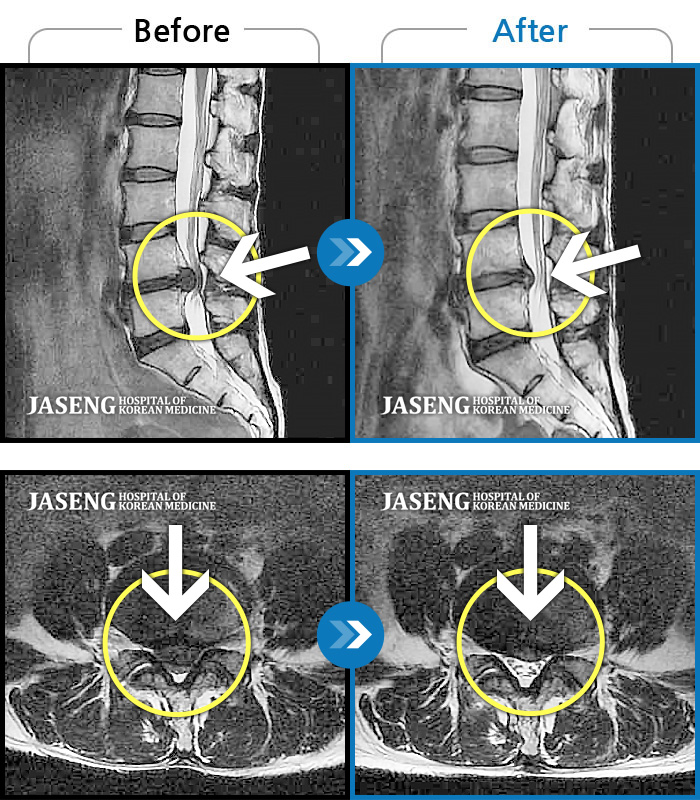

허리디스크

많이 본 사례

수원 · 김태성 원장

허리 통증과 좌측 대퇴부 저림과 당김

촬영시기

2023.02.03 ~ 2024.02.14

2024.11.21

조회수 460